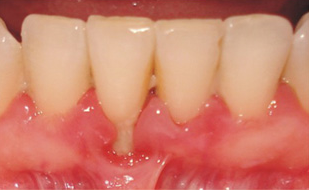

Sağlıklı Dişeti Görüntüsü Nasıldır?

Sağlıklı dişeti, genellikle açık pembe renkli, mat, yüzeyi portakal kabuğu görünümünde, sert kıvamlı (kanaması olmayan) ve diş yüzeyinde kalınlaşmadan bıçak sırtı gibi sonlanan özelliklere sahiptir.